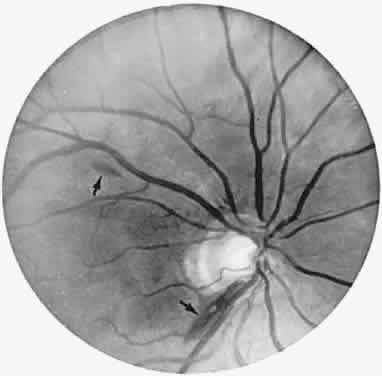

Fig. 9. An 18-year-old student with recurrent episodes of left retinal migraine. After a typical attack, he noted an inferior field defect. A. Fundus shows a defect in the superior arcuate nerve fiber bundle (between arrows: compare fiber layer below disc). B. Visual field defect corresponds to a retinal nerve fiber layer defect.